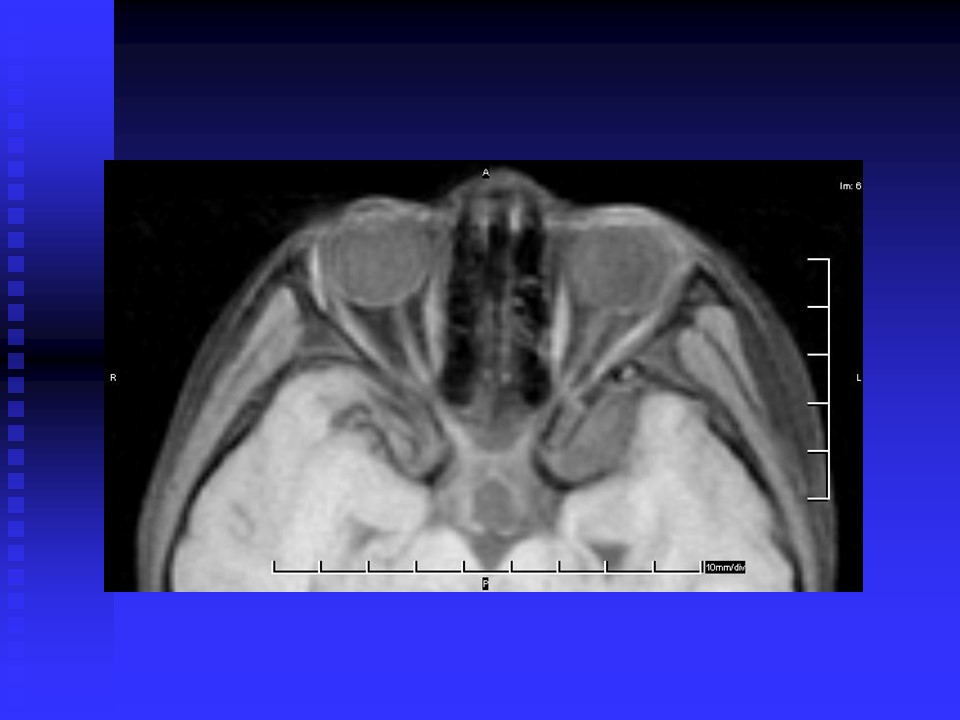

“头颅MRI读片知识” 的相关文章